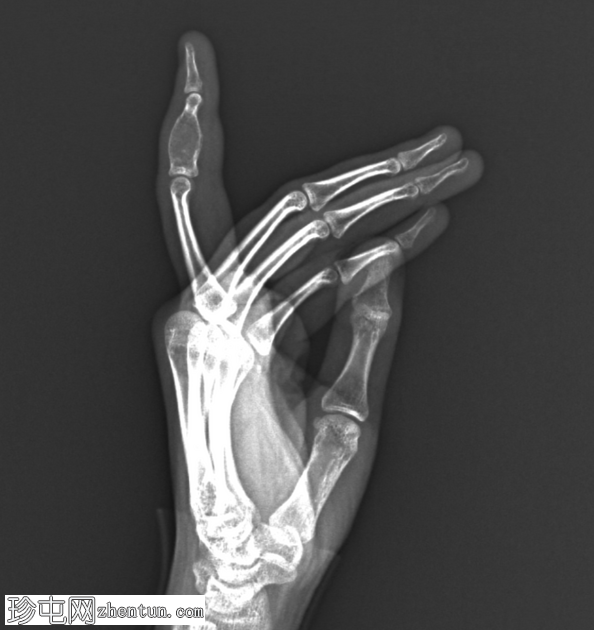

2.png

侧位片

左手食指中节指骨可见一边界清晰、膨胀性髓内溶骨性病变。病变表现为骨内膜凹陷伴轻度皮质变薄,但未见皮质破裂。软骨基质钙化呈淡点状。未见骨膜反应或邻近软组织肿块。未见病理性骨折。邻近的近节和远节指间关节结构完整。其余可见骨骼密度和排列正常,未见其他病变。